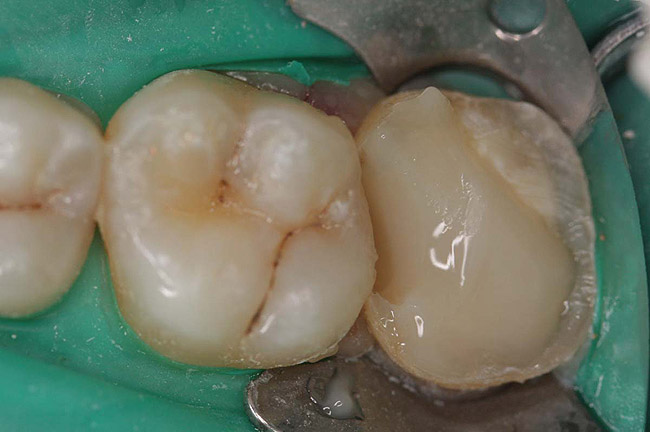

Figure 9  Cure core material placed without a matrix.

Figure 9